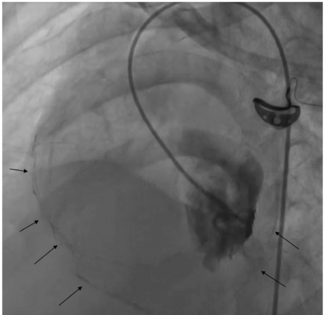

A 55-year-old Thai man with history of chronic alcoholism presented to our hospital complaining of sudden onset of severe substernal chest pain and profuse sweating for 4 hours. Upon arrival, he was barely conscious. His initial blood...